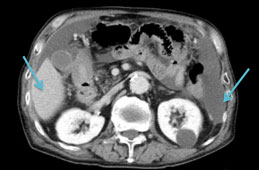

明確な診断を下すためにいくつかの検査を要求する場合があります。画像検査は、腹膜内の異常な塊や肉芽を探すのに役立ちます。これらのテストには次のものが含まれます。

• 超音波:これは通常、医師が癌性肉芽を検出するために使用する予備検査です。ただし、超音波検査では大きさが2センチメートル未満のものは識別できません。肉芽だけでなく、腹水、癒着、リンパ節腫脹 (リンパ節の腫れ) などの他の特徴も検出できます。

• CT スキャン: 5 ミリメートルほどの小さな肉芽を確認できます。

• MRI スキャン: MRI スキャンは、小さな腹膜癌腫症の検出において CT スキャンよりも感度が高くなります。これらは、状態を診断し、病期分類するために選択されるモダリティです。